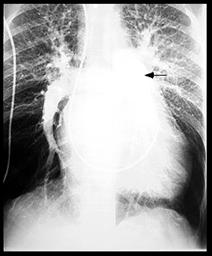

3. Rx. poate arata:

o silueta cardiaca mitrala,

largirea AS (PA, OAS, LS),

dublu contur dr.,

calcificari mitrale sau de AS,

VS mare sau mic,

semne de hipertensiune veno-capilara:

redistributie venoasa lobara sup,

edem interstitial,

linii Kerley exprima staza limfatica (A-la hil, B-la baza SM stransa, C-intre),

edem alveolar,

epansament pleural.

hemosideroza,

calcificari

pulmonare,

infarct pulmonar,

alte boli pulmonare

asociate.